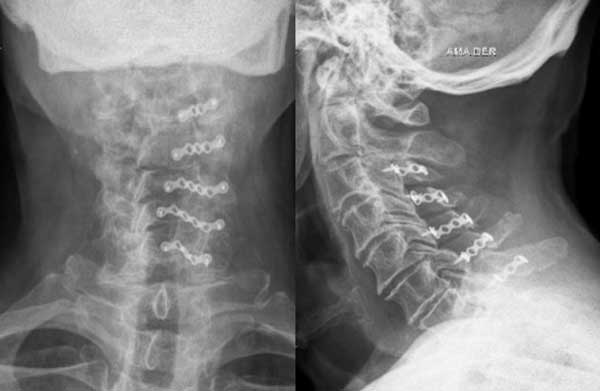

Paciente masculino de 72 años, con tetraparesia severa de instauración aguda secundario a latigazo cervical. Al examen físico: tetraparesia severa asociado a hipoestesia en 4 miembros a predominio de miembros inferiores y globo vesical. Nurick prequirúrgico de 5. En RM se observó una disminución del diámetro del canal cervical asociado a signos de edema medular (Figuras 8 y 9). Se propuso efectuar una laminoplastia entre los niveles C3-C7. No se evidenciaron cambios en la escala de Nurick.

Figura 9. Imágenes radiológicas cervicales postquirúrgicas en proyección anteroposterior y lateral.